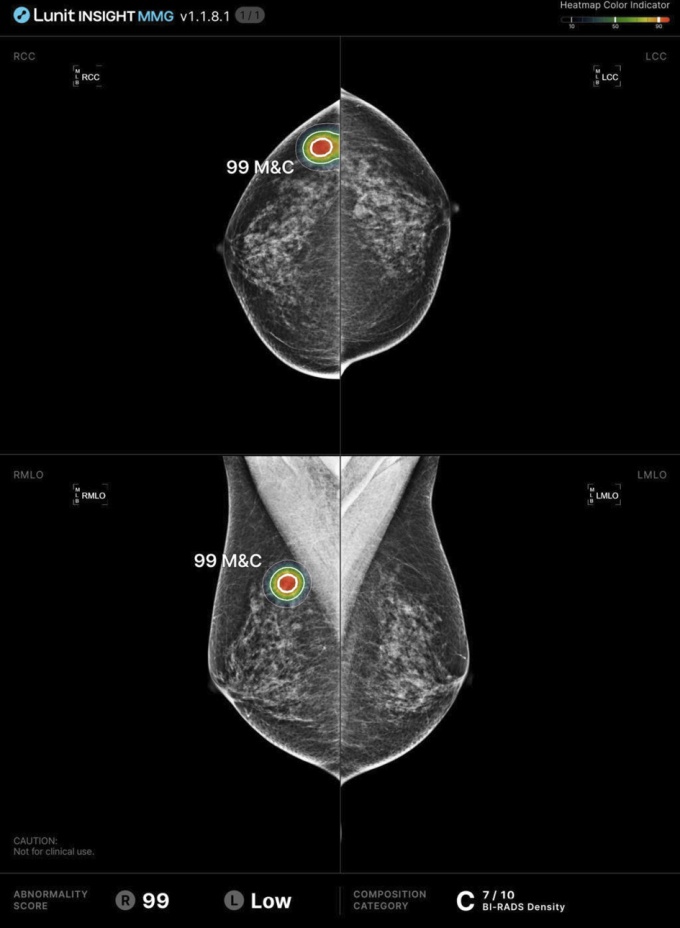

Die ScreenTrustCAD-Initiative ist als prospektive, bevölkerungsbasierte klinische Studie mit Paired-Reader- und Non-Inferiority-Design angelegt. Zwischen April 2021 und Juni 2022 wurden über 55.000 Frauen im Alter von 40 bis 74 Jahren, die an einem staatlich organisierten Screening teilnahmen, untersucht. Jeder Mammographie-Datensatz wurde parallel von zwei menschlichen Radiologen sowie einem KI-System (Lunit INSIGHT MMG) bewertet. Durch das gewählte Studiendesign lässt sich genau berechnen, wie das Screening abgeschnitten hätte, wenn entweder der Radiologe oder die KI nicht an der Befundung beteiligt gewesen wäre.Die zentrale Fragestellung: Kann eine KI einen menschlichen Befunder ersetzen, ohne die diagnostische Qualität des Screenings zu beeinträchtigen?

Die Datenantwort ist klar: Ja. Die Kombination aus einem Radiologen und KI war nicht unterlegen und zeigte sogar eine leicht höhere Krebsdetektionsrate als das klassische Doppelbefundsystem mit zwei Radiologen – 261 vs. 250 entdeckte Fälle, was einem relativen Zuwachs von rund 4 % entspricht. Auch bei einem reinen KI-Einzelbefund lagen die erzielten Erkennungsraten praktisch auf dem Niveau zweier Menschen.

Im ScreenTrustCAD-Workflow zeigte sich zudem, dass Entscheidungen, bei denen die KI einen Befund markierte, eine höhere positive prädiktive Wertigkeit (PPV) aufwiesen, als allein manuelle Entscheidungen – ein Hinweis darauf, dass das KI-System nicht nur quantitativ misst, sondern auch qualitativ robuste Hinweise liefert.